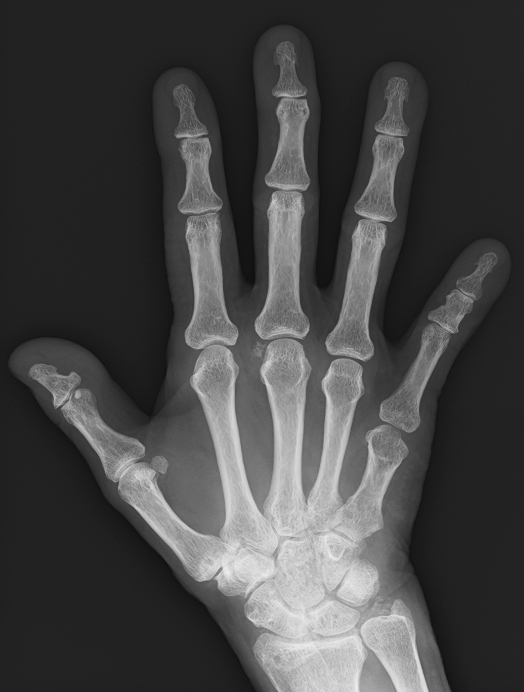

一般撮影室  胸部 手背 腹部XP

健診などでよく目にすることがある胸部や腹部、骨などを撮影するエックス線撮影、CT検査、MRI検査やPET-CT検査、また女性にとって関心が高いマンモグラフィー、骨密度検査、そして体を切ることなく治療を行う、血管内カテーテルによるIVRや高エネルギー放射線照射による放射線治療(リニアック)など多岐にわたり、現代医療の診断・治療には欠かせない部門となっております。

当院の一般(レントゲン)撮影はすべてデジタル化されており、従来のフィルムを使用しないため、診察場への画像提供までの待ち時間がかかりません。